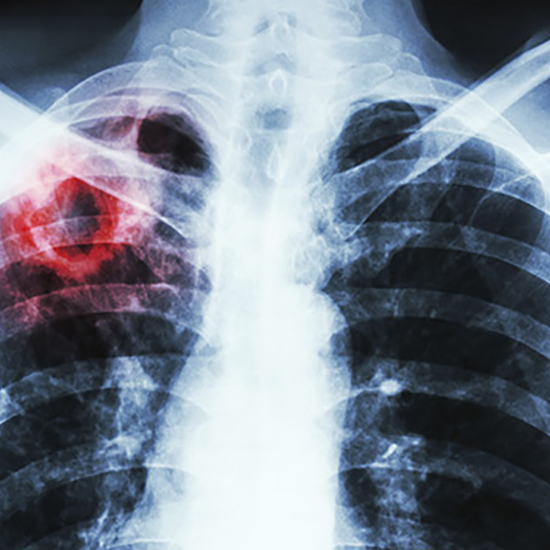

Туберкульоз — небезпечна хвороба. Симптоми можуть бути непомітними впродовж багатьох місяців, тож люди часто звертаються за допомогою на пізніх стадіях. Несвоєчасне звернення до лікаря призводить до подовження терміну лікування та виникнення ускладнень захворювання. Небезпека також криється в тому, що один хворий на туберкульоз, який не знає про свій діагноз і не отримує лікування, може за рік заразити близько 10–15 людей.

Туберкульоз важливо виявити на ранній стадії, адже тоді пацієнт може з перших днів розпочати лікування амбулаторно з дотриманням заходів інфекційного контролю. У разі відсутності бактеріовиділення та клінічних проявів хвороби пацієнт може ходити на роботу або навчання. Тож важливо, щоб люди за появи перших симптомів туберкульозу (кашель понад 2 тиж, різке схуднення, нічна пітливість, слабкість) зверталися до свого сімейного лікаря.